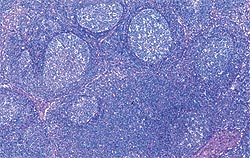

| Allure normale | Légère perturbation de l’architecture folliculaire |

| Perturbation modérée de l’architecture folliculaire | Perturbation intense de l’architecture folliculaire |

Déplétion lymphocytaire et infiltration granulomateuse légères, modérées et intenses comparées à un ganglion de structure histologique normale. Les lésions modérées et intenses sont indicatrices de la MAP. Coloration HE.